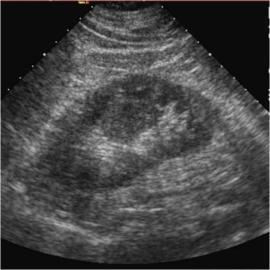

Медицинские изображения: колонна Бертини на КТ